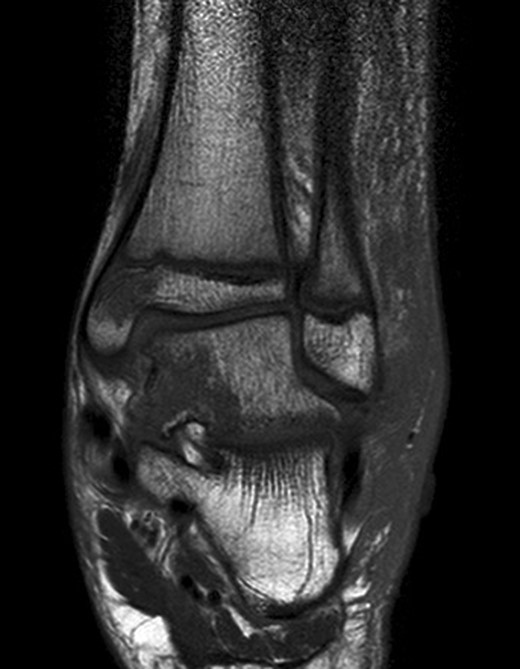

At 12 weeks follow-up, the patient was weight bearing comfortably with near full range of movement. A repeat CT and MRI scan showed no evidence of displacement of the fracture fragments with good evidence of talus fracture healing. MRI revealed reduction in bone marrow signal changes with no evidence of subchondral collapse (Figs 4 and 5).

12-week follow-up MRI scan confirms reduction in bone marrow oedema in injured medial tibio-talar joint.